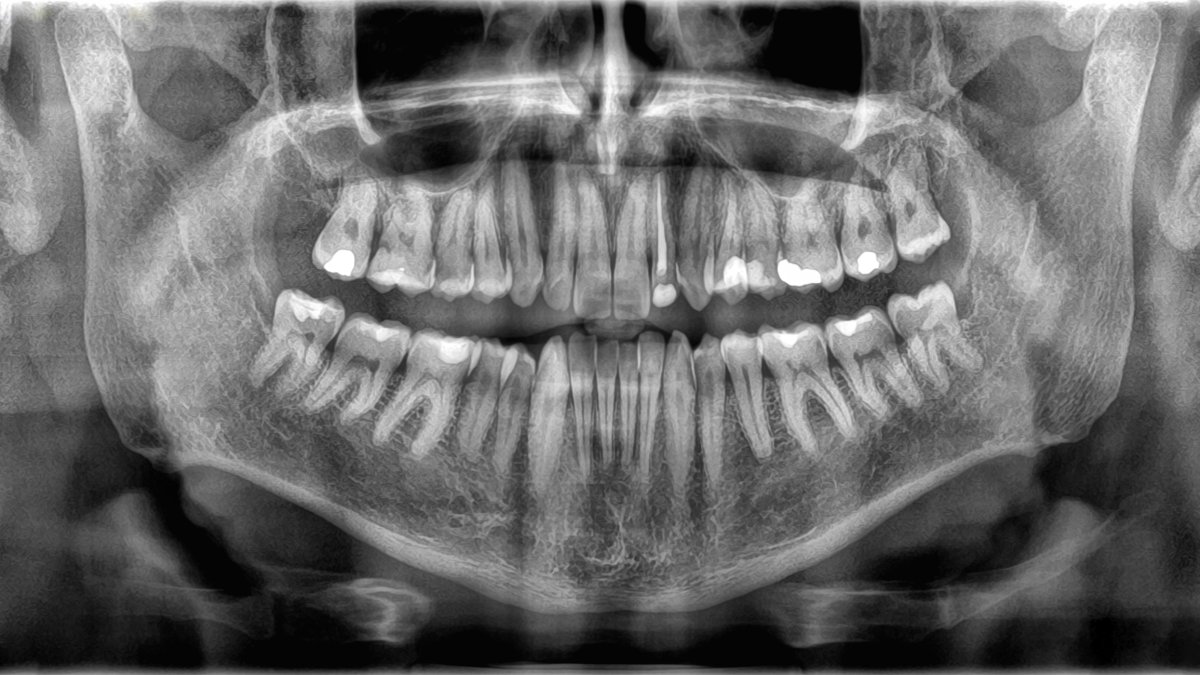

dientes

La pérdida de dientes podría ser algo más que una molestia asociada al paso del tiempo. Un estudio reciente de la Universidad de Sichuan (China) ha encontrado que las personas mayores que pierden dientes con rapidez presentan un riesgo significativamente mayor de mortalidad que aquellas que los mantienen durante más tiempo. El hallazgo, publicado en la revista BMC Geriatrics, sugiere que el estado bucal podría ser un reflejo directo de la salud general y una señal de alerta temprana ante otras enfermedades graves.